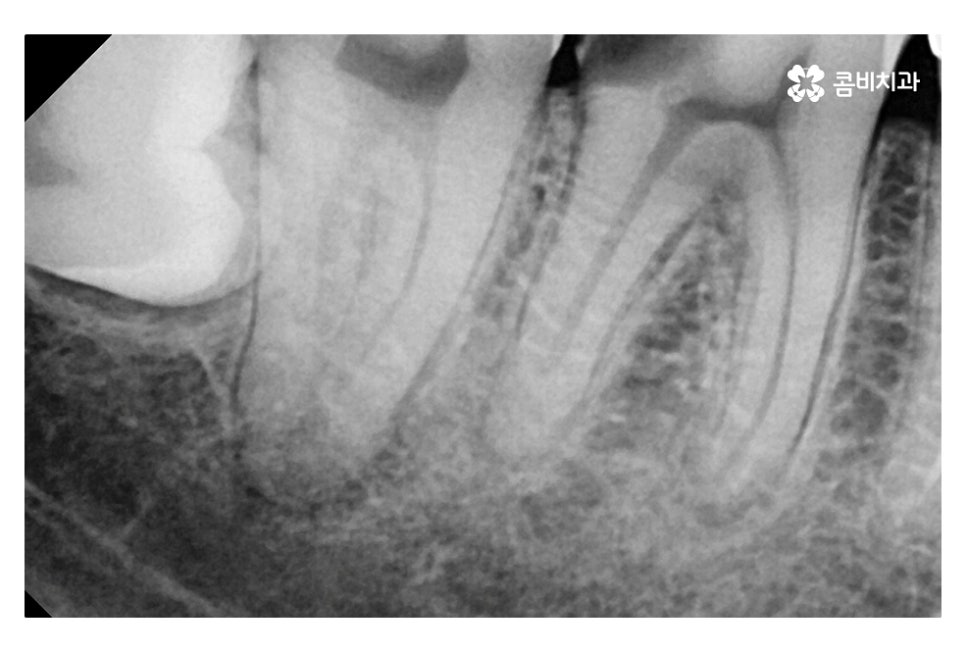

위 사진은 신경을 제거한 후 치과용 재료(GP cone)로 채워 넣은 상태인데

신경치료 후 크라운 치료를 하는 과정은

치아의 신경관을 찾아 미세한 신경 조직을 깨끗하게 제거해야 하며

자연치아를 살리는 중요한 단계라고 볼 수 있어요.